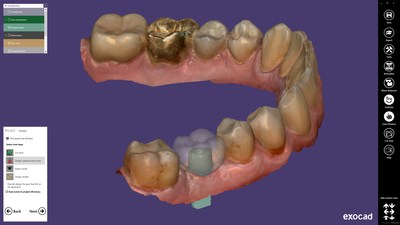

DARMSTADT, Germany, Nov. 14, 2019 /PRNewswire/ — exocad GmbH announces the release of the latest software version ChairsideCAD 2.3 Matera. ChairsideCAD, the first hardware-neutral CAD solution for the clinical environment, was first launched last year. With the new release, the company is now offering the widest range of indications in the market for chairside CAD software and at the same time covering the broadest spectrum of integrated devices. The software is intuitive, so users can easily, economically and reliably deliver esthetically demanding restorations in a single patient session.

With the new ChairsideCAD 2.3 Matera modules, the software can intelligently expand the individual practice’s offerings. Smile Creator is the ideal tool for 2D / 3D esthetic planning of restorations, ensuring predictable results. Model Creator is suitable for creating physical models from digital impression scans. With Jaw Motion Import, patient-specific jaw movements are imported from various measuring systems and used directly for optimal design of the occlusal surface. The DICOM Viewer impresses with its outstanding speed when loading CB/CT images, which can be visualized together with intraoral scans and construction data. In addition, patient photos and three-dimensional facial scans can be used in combination to create a comprehensive fully digital representation of the patient.

The Implant Module enables the design of abutments, screw-retained crowns and bridges. The software and its modules are integrated on exocad’s proven and robust software platform, which has been successfully used for more than ten years. This has several advantages: ChairsideCAD Matera always runs reliably – even with complex restorations – and follows the same intuitive operating workflow as all exocad software applications. The wizard-driven user guidance allows precise results to be achieved quickly and with impressive quality. The combined platform with the world’s leading CAD laboratory software exocad DentalCAD also opens up unparalleled possibilities for digital collaboration with tens of thousands of laboratories. If so desired, each step of the digital workflow can be outsourced to a preferred laboratory, allowing dentists to save time and rely on the expertise of their partner.